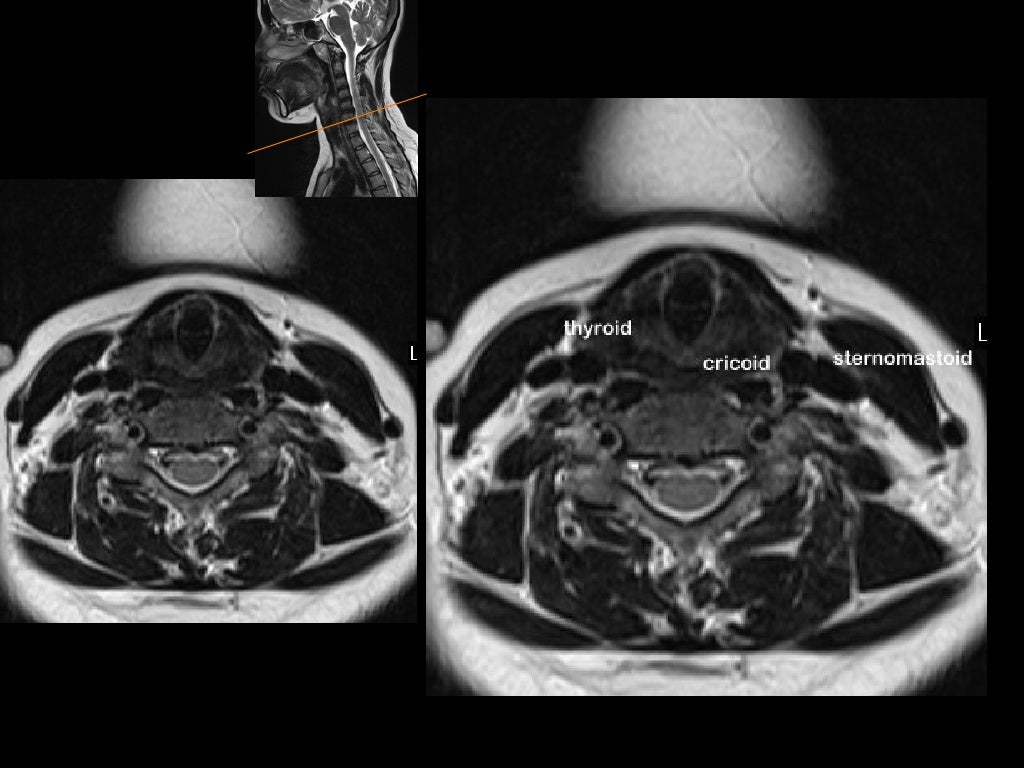

From radiologykey.com

Neck MR Imaging Anatomy Radiology Key Can Ms Be Seen On Neck Mri mri criteria for ms are based on the presence of focal lesions in the white matter (wm) of the central nervous system. ms symptoms can mimic many other health issues. Ms lesions can appear in. Typical ms lesions tend to be oval or frame shaped. there are a number of different images that can be taken during. Can Ms Be Seen On Neck Mri.